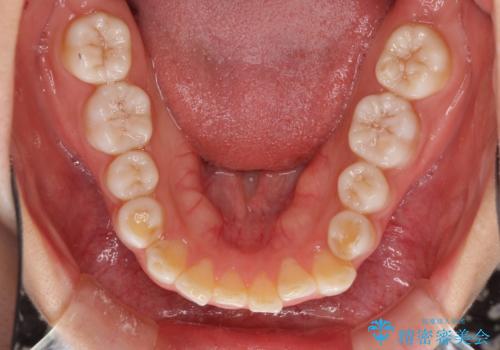

インビザラインによる軽度な出っ歯の矯正治療

- 上の前歯の出っ歯を治したいとのことで来院された患者様です。

上下顎ともにIPR(歯と歯の間を削る)と歯列全体の拡大によって口元が引っ込むように設計し、インビザラインにより治療を行うこととしました。

どこまで口元を引っ込めることができるのか、患者様自身も正直分からない部分があったため、少しずつ治療ゴールを変更しながら仕上げていきました。

気になっていた前歯の飛び出した印象は、最終的にはスッキリと引っ込み、大変満足していただきました。